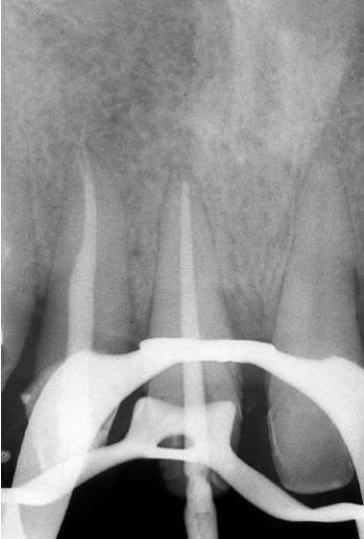

Về mặt giải phẫu học, răng cối nhỏ thứ nhất trên có thể có hình dạng hoàn toàn khác. Ống tủy cong hình lưỡi lê ở 1/3 chóp chân răng là một dạng điển hình. Hiếm khi tìm thấy một ống tủy đơn, hình elip trong một chân răng; thường gặp hai ống tủy giao nhau ở 1/3 giữa với hai lỗ chóp trong một chân răng (38%) hoặc hai ống tủy (thường cùng chiều dài) ở trong hai chân răng riêng biệt (60%). Hiếm hơn nữa có thể thấy ba chân răng với ba ống tủy và những lỗ chóp riêng biệt, chiếm 6% theo Carns và Skidmore , và 5% theo những tác giả khác. Trong những trường hợp này, RCN có hình dạng như răng cối lớn. Một ống tủy rộng hơn ở phía trong và hai ống nhỏ hơn ở phía ngoài, một ở phía gần và một ở phía xa (hình 11.46). Điều trị nội nha tốt hay không phụ thuộc vào việc tạo xoang tủy có đúng hay không: răng cối nhỏ trên với ba ống tủy thì cần tạo một xoang tủy có hình dạng chữ “T” với sự mở rộng theo chiều gần xa ở phần ngoài của xoang truyền thống. Sự thay đổi này cho phép tạo một đường vào tốt cho cả hai ống tủy ngoài. Nếu ba chân răng phân kỳ, ta có thể thấy được trên phim X-quang trước điều trị. Nếu ba chân răng chụm hoặc chồng lên nhau (hình 11.47A), ta có thể biết được trong lúc điều trị. Nha sĩ có thể nghi ngờ có hai ống tủy ngoài không chỉ nhờ vào sự hiện diện của 2 miệng ống tủy (thường không nhận ra hai miệng ống tủy riêng biệt), mà còn nhờ vào hướng của cây trâm thăm dò khi nó đi vào một trong hai ống tủy, hoặc hình dung trên phim X-quang thấy hình ảnh dị dạng nhưng những đường nét chung của chân răng vẫn bình thường [ví dụ: hoàn toàn nằm về phía gần (hình11.47 B)], ta có thể nghi ngờ còn một ống tủy ngoài thứ hai nữa mà hướng của nó nằm về phía xa hơn so với ống thứ nhất (hình 11.47 C, D).

Hình 11.47. A. Phim trước điều trị răng #14: Chân răng chồng lên nhau, không dễ nhận ra ba ống tủy. B. Dụng cụ đầu tiên được đừa vào miệng ống tủy (dường như là ống ngoài), hình ảnh dụng cụ đi theo một hướng bất thường so với hình ảnh chân răng. Nhìn kỹ thấy nó chuyển hướng về phía gần: dụng cụ đã đi vào ống gần ngoài. C. Uốn cong dụng cụ về phía xa rồi đưa vào cùng miệng ống tủy này, nó tự động đi vào ống xa ngoài. D. 34 tháng sau, phim X-quang cho thấy sự hiện diện của ba ống tủy.